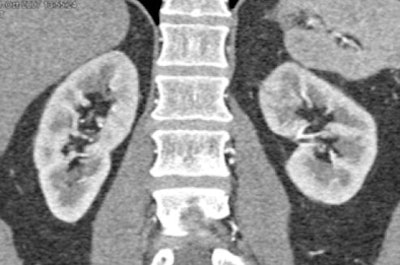

In one patient example, a small hypervascular lesion in the left kidney could not be seen in the early corticomedullary phase, even when the image was viewed in multiple planes, in volume rendering (VR) and maximum-intensity projections (MIPs). It became "a fairly obvious lesion on excretory-phase imaging," Fishman said.

| Subtle renal cell carcinoma not visualized in any plane in the arterial phase (above) becomes fairly obvious in excretory-phase image (below). All images courtesy of Dr. Elliot Fishman. |